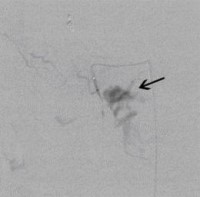

Postoperative abdominelle Blutungen bei chronischer Pankreatitis nach Embolisation der Art. gastroduodenalis mittels Metallspiralen (Coils)

(Bild 3 von 5)

Perkutane Embolisation einer low-flow venösen Malformation (Gefäßmissbildung) der Fußsohle-1

(Bild 4 von 5)